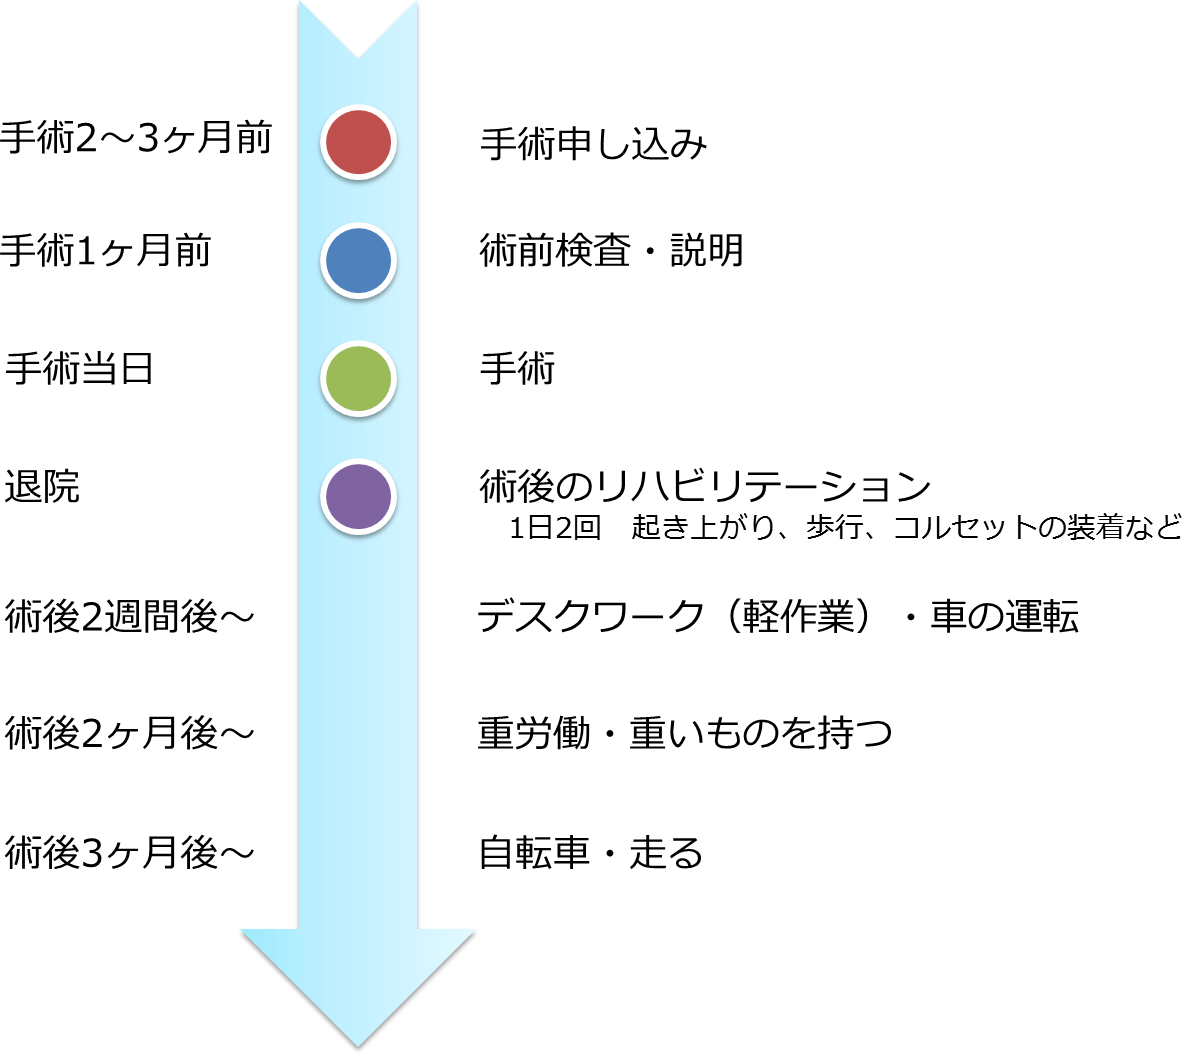

手術前から退院後までの流れは?